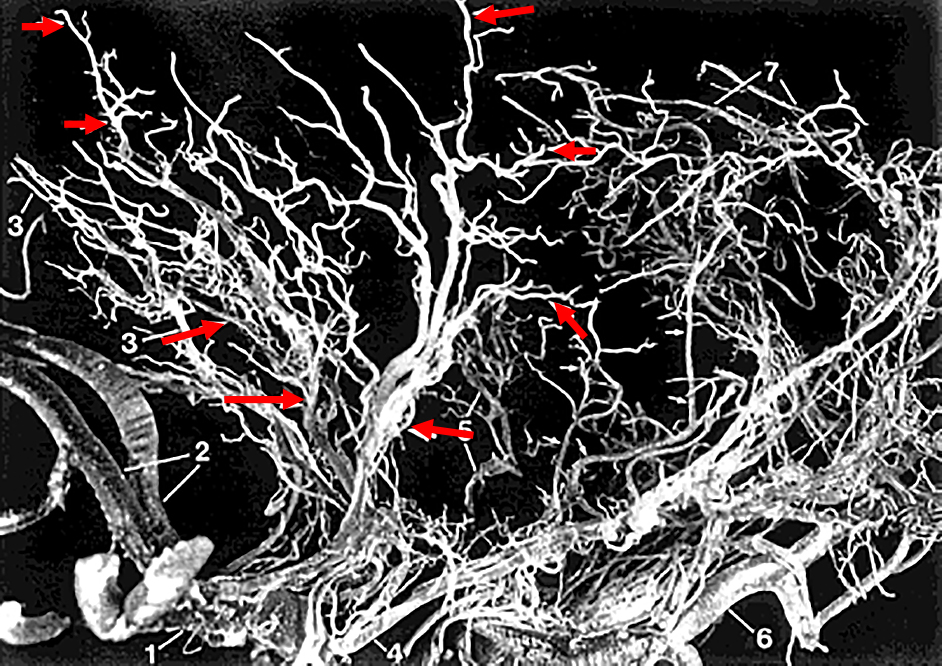

Fig. 1

The three different groups of lenticulostriate artery (LSA) arising from the main trunk of middle cerebral artery (MCA).

The medial (A), intermediate (B) and lateral branches (C). Reprinted from the figure in the article of 4) with permission.

LSAは分岐直後,medial(平均2本),intermediate(平均3本),lateral(4~5本)の3群からなり,前有孔質を通過して脳実質内に入る.前有孔質を通過する際に,各々,4本,14本,8本に枝分かれする(Fig. 14.脳実質内ではこれらが内側と外側の2群に分かれるが,Marinkovićらによれば,medialはそのまま内側群となり前後に広がって,尾状核頭部,内包前脚の一部,後脚の前下部,被殻の内側・淡蒼球の後方を灌流する7.Intermediate, lateralは外側群をなすが,intermediateは外側前方枝群,lateralは外側後方枝群となる.外側群の支配領域は,被殻の大半,淡蒼球の外側,尾状核頭部の上方,内包前脚,内包膝部・内包後脚の上部全体,境界領域としての放線冠などを支配する910.LSAの分岐はM1の外側になるほど急峻な角度をなして,M1の血流方向と逆方向すなわち内側に走行する.圧負荷に対する適応と思われる711

LSAは,内側から外側にかけ同一平面に並んでいるのではなく,内側は前方に傾き外側は上後方に向かって走行し,全体として扇をねじったような立体構造を形成する7.したがって,内側の分枝は前方に,外側の分枝は後方に分布する.前方枝と後方枝の角度は近位部で約44°(28°~80°),扇のより遠位部では114°(97°~128°)とされるが,LSAはねじれ構造で前後にも一定の広がりを持っている点が血管支配を考える上で重要である(Fig. 211